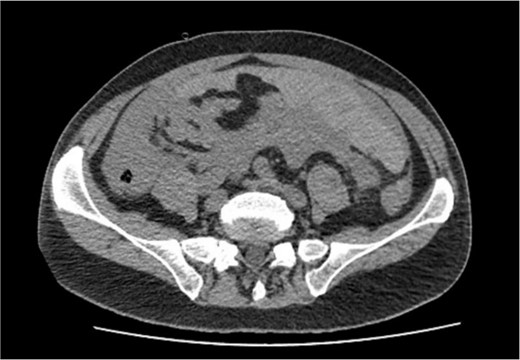

The patient was pale, hemodynamically stable, and with signs of peritoneal irritation. His hemoglobin was 15.1 g/dL. Contrast enhanced CT demonstrated 11.6 × 8.8 × 16.5 cm3 intramural hematoma in anterior stomach wall with active bleeding and hemoperitoneum (Figs 2 and 3). Exploratory laparotomy was done after optimizing the patient.